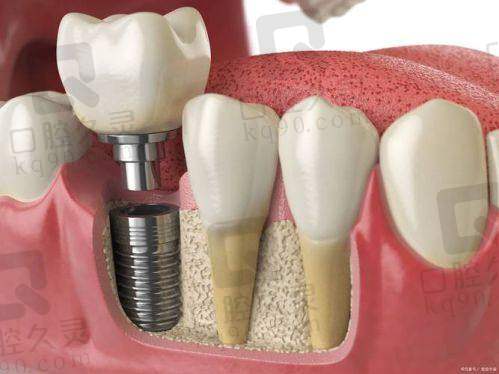

西宁诺贝尔口腔采用的是集成数字化种植体系——三维口腔CT、种植导板系统、口扫设备等一应俱全。尤其是数字化导板技术,能精细定位种植位置,就算是牙槽骨吸收也能放心大胆去种。

手术采用微创种植技术,减少传统“翻瓣手术”的不适感,术后修复快、肿胀小、几乎不影响正常生活节奏,非常适合怕痛星人或老年人。